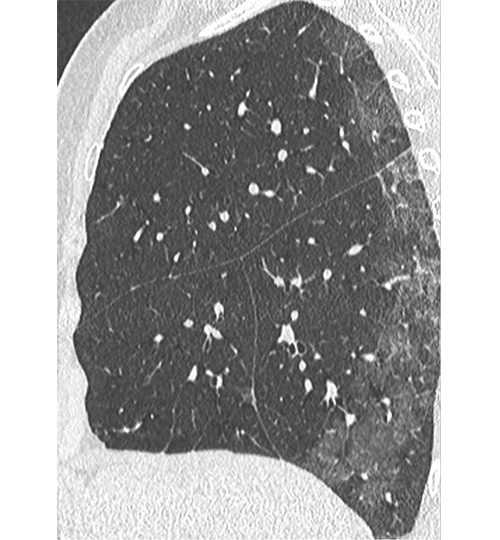

Image : Tomodensitométrie. Patiente de 71 ans sans antécédent, atteinte de Covid-19, ayant une pneumopathie interstitielle. Aspect typique initial : atteinte bilatérale à type de verre dépoli périphérique sous-pleural. Crédit : Société française de radiologie (https://bit.ly/39NaivY).